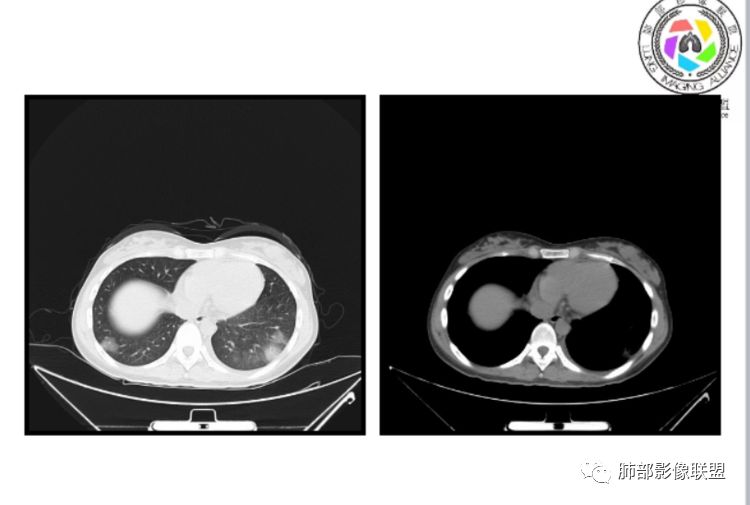

小微:右肺下叶斑片状密度增高影,抗炎治疗6天后复查,双肺下叶出现斑片状密度增高影,排除炎性病变,D2聚体特别高,考虑肺栓塞,肺梗死,建议增强扫描。王开金江津中心医院呼吸科:@岳微-辽宁PLA234医院放射科?支持,患者年轻女性,胸痛主诉,使用雌激素,高危人群,心率快,d二聚体升高,右下叶斑片加肺动脉明显增宽,抗感染无效,要考虑PTE,建议肺动脉ctpa。傅昌瑜:19岁,女性,右侧胸痛2天,发热以中度热为主,D—二聚体升高,肺动脉主干增宽,病灶位于胸膜下,抗感染后增多,近来有服用炔雌醇环丙孕酮片2周期史,诊断:肺栓塞,下一步完善肺CTPA检查。阿仙奴:青年女性,急性起病,胸痛入院,月经不调史,目前服用孕酮片。流感抗体阳性,d二聚体升高,无低氧血症。右肺下叶基底段胸膜下磨玻璃样改变,肺动脉增宽,治疗过程出现发热,复查左下叶胸膜下新发病灶。考虑:肺栓塞(服用孕酮相关)?奔跑的37°Doctor(陆喜红 ) :年轻女性,胸痛 急性病程,有服用雌激素避孕药史(是否有血液循环的改变,高凝状态),实验室D二聚体很高(也是提示血液高凝状态) ,第一次CT,右下肺胸膜下斑片状密度增高模糊影,肺动脉形态密度未见明显异常,抗炎后复查,肺动脉干及其分支,感觉增粗了一点,局部形态有点饱满,双下肺胸膜下片状影增多,锁定肺动脉栓塞应该不会错,建议CTA检查飞鹰行动:青年人,女性,右肺下叶斑片状密度增高影,抗炎治疗6天后复查无好转,,双肺下叶出现斑片磨玻璃影,主肺动脉增粗,结合患者服用的药物和D2聚体特别高,考虑肺栓塞,建议CTA。李:口服避孕药,有危险因素,肺动脉较主动脉增宽,D二聚体增高,胸膜下片状影,考虑肺栓塞;@晨义工张帅,医附属潞河医院呼吸?是否痰中带血很关键,不知有没有张帅:患者入院后第七天出现痰中带血风之子:病程中有发热,D—二聚体升高,肺动脉主干增宽,病灶分布于胸膜下,抗感染后增多,结合服药史诊断:肺栓塞,建议CTPA检查。不支持的地方是没有低氧血症,不明白为什么第二次复查ct双侧乳腺不对称,按理乳腺炎多见于哺乳期张帅:大家方向都在考虑肺栓塞:我提问两个问题:1 周围毛玻璃怎么回事?2左下肺小叶间隔增宽怎么回事?笨丫头:周围的磨玻璃应该考虑是肺梗死后出血渗出,同时合并机化性炎症小叶间隔增宽,我考虑应该是梗死后炎性渗出wonderful:我不支持肺栓塞 不能解释发热原因

水晶石头:患者青少年女性,右侧胸痛2天就诊。有咳嗽,无痰。初次胸部CT:右下肺片状模糊影。入院后经头孢美唑、莫西沙星抗感染治疗6天后复查胸部CT:右下肺病灶加重,且左下肺出现类似病灶。结合其气管镜气道无异常,病程中有发热,D—二聚体升高,近来因月经不调有服用炔雌醇环丙孕酮片史。诊断考虑良性非感染性。肺栓塞可能性大,鉴别血管炎及子宫内膜肺异位可能。流心明智:女性,19岁,右侧胸痛2天,中度热为主,D—二聚体升高,影像:肺动脉主干小于29mm,病灶位于右下肺胸膜下,斑片影,胸膜侧宽基底,抗感染后增多,左下肺亦出現类似病灶,似有反晕、融冰征。近来有服用炔雌醇环丙孕酮片2周病史,考虑诊断:肺栓塞。具体性质及发病机制有待进一步检查。尘缘:@吴永丽 灌云县医院 呼吸?应该是的,左下肺的磨玻璃影像后面也支持有出血改变所以可能就是一个子宫内膜异位出血合并感染

没意见:同意各位老师高见,临床D二聚体比这个高的多了,这个指标只能作为筛选条件,就这个病例来说,指向性还是比较明显的,没看出还有别的可能wonderful:d2聚体阴性有排除意义 阳性与数值意义不大天涯:感染有,是不是和栓塞有关?还要CTA,子宫内膜异位思路很好不倾城不可爱:会不会子宫内膜异位症呢采莲:青年女性,有口服避孕药病史,双下肺胸膜下多发斑片磨玻璃影,有融冰征,二聚体高,还是首选肺栓塞可能性大。至于子宫内膜异位症见得少。崇军:第一次点晕征,六天以后加重,而且左下肺病灶明显增大,磨玻璃,pct正常,抗感染无效,所以感染性病变排除。肿瘤性病变,太年轻,暂排。血管炎,化验为阴性。少见病子宫内膜移位不会六天以后加重。结合化验指标,还是肺栓塞可能南边:曹老师考虑子宫内膜异位症?有没有考虑肺栓塞的?我们下一步该如何处理?

1、一个或多个胸膜下斑片高密度影(梗死、出血、肺不张、肺水肿、炎性渗出),典型为胸膜下楔形影 ,尖端指向肺门

3.影像:病变胸膜下多发斑片影,提示与血管有关,早期病变为渗出,应该是早期的炎性渗出,病灶抗感染治疗后实变区增多、变大,临床症状又出现咯血,CT上应该合并了肺泡出血、梗死、肺不张及肺水肿;